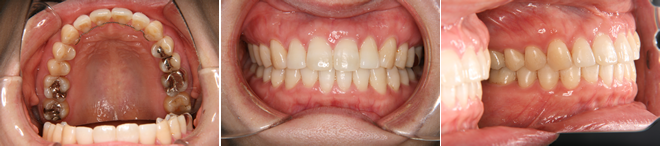

| 主訴 | 噛み合わせが逆、八重歯 |

| 年齢・性別 | 20歳 / 女性 |

| 治療方針 | オトガイの突出感が強く、顔貌改善には外科矯正が適応と考えられたが本人が希望しなかったため、マルチブラケット装置のみで治療を行った。 |

| 抜歯部位 | 上下顎左右小臼歯(計4本) 治療後に下顎左右第3大臼歯(親知らず) |

| 使用装置 | マルチブラケット装置 |

| 治療期間 | 27か月 |

| リテーナー | 上顎インビジブル、下顎スプリングリテーナー |

| 費用 | 825,000円(税別) |